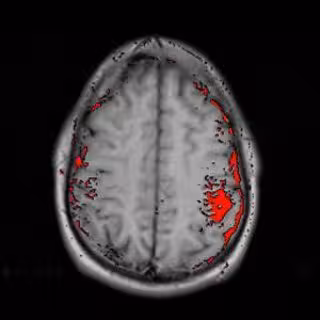

Un equipo de la Universidad de Kuopio (Finlandia) ha conseguido determinar si una persona tiene placas amiloides, principal síntoma indicativo de la enfermedad de Alzheimer, a través de imágenes obtenidas con tomografía por emisión de positrones (PET), según demuestra un estudio publicado en la revista 'Archives of Neurology'. Por lo general, los médicos no pueden identificar las placas hasta que el cerebro es analizado en la autopsia.

Esta tecnología podría permitir el diagnóstico del Alzheimer en fases iniciales y paliar a través del tratamiento farmacológico el deterioro cognitivo asociado a esta enfermedad.

El estudio involucró a diez personas que habían sido sometidas a una biopsia cerebral por un supuesto aumento anormal del fluido cerebroespinal. Los pacientes se sometieron a una tomografía PET que, tras la inyección de un marcador químico, consiguió determinar correctamente en nueve de los diez pacientes cuáles tenían placas amiloides y cuáles no.

Ninguna de las diez personas que participaron en el estudio había desarrollado una demencia severa en el momento de someterse a las pruebas. Sin embargo, tras las tomografía se detectó que seis de las personas presentaban placas indicativas de un estadio precoz de la enfermedad de Alzheimer.